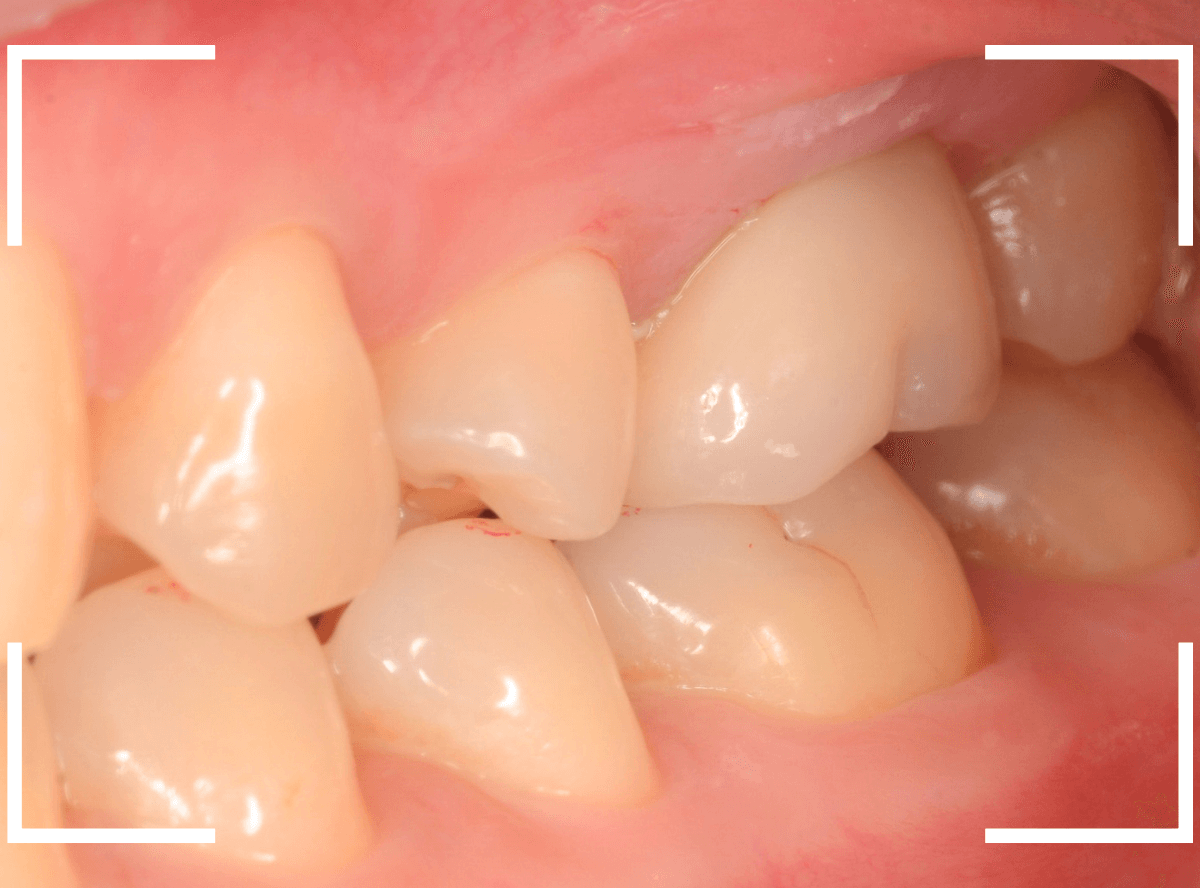

治療前後の比較写真になります。